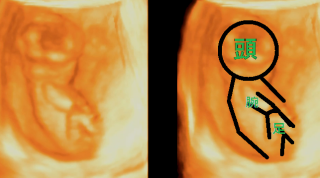

横向きの4Dです。下の子のときには4Dはありせんでしたので、はじめてみた4D、白黒とは違いすごく手や足がわかりやすかったです。

出血してお腹も痛くなってきて、日曜日だったけど病院に電話をして見てもらいに行きました。前回流産をしてるので泣きそうになりながら 診察台へ。ながい沈黙あと‥赤ちゃん元気ですよ!!との言葉を聞いて涙がでました。エコーを見せてもらうと、ガッツポーズをしたあと手を振ってるように見えました(*^^*)赤ちゃんも頑張ってるんだね。生きててくれてありがとう。

指しゃぶりをパパラッチに狙われたようなポーズです(笑)